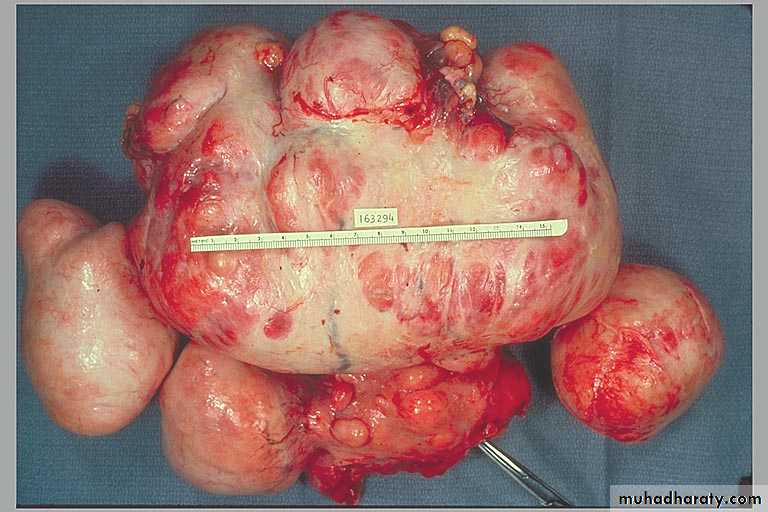

Markedly distorted uterine corpus with multiple irregular masses protruding from its surface. These are subserosal leiomyomata.

Leiomyomas uteri

They are sharply circumscribed, firm gray-white masses with a characteristic whorled cut surface.They may occur singly, but are often multiple tumors scattered within the uterus, ranging in size from small seedings to massive neoplasms that dwarf the size of the uterus.

Some are embedded within the myometrium (intramural), whereas others may lie directly beneath the endometrium (submucosal) or directly beneath the serosa (subserosal).

Multiple uterine leiomyomas.

Smooth muscle tumors of the uterus are often multiple. Seen here are submucosal, intramural, and subserosal leiomyomata of

the uterus.